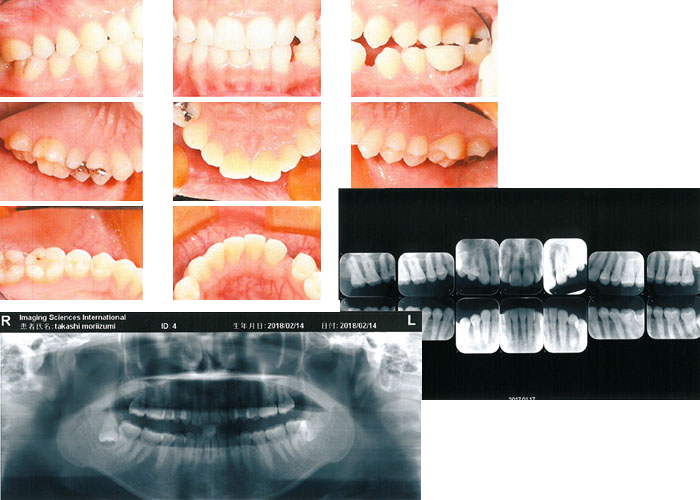

まず、自分のお口の中の状態を知ることが第一歩です。当院で撮影したお口の中の写真9枚やパノラマレントゲン写真1枚、デンタルレントゲン写真12枚を見てみましょう。

どこの歯に虫歯があって、どこの歯を治療しているのか、歯周病の進行状態はどの程度なのか、自分の噛み合わせはどういう状態なのか。まず、自分のお口の中に興味を持ち、知ることから始めましょう。